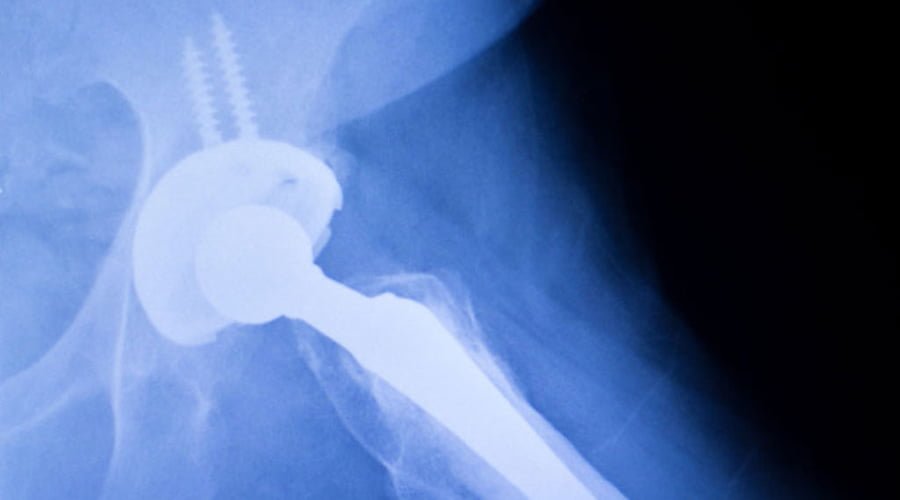

Endoprotezoplastyka stawu biodrowego to zabieg chirurgiczny polegający na wszczepieniu do stawu biodrowego sztucznych elementów. Celem jest poprawa jakości życia pacjenta